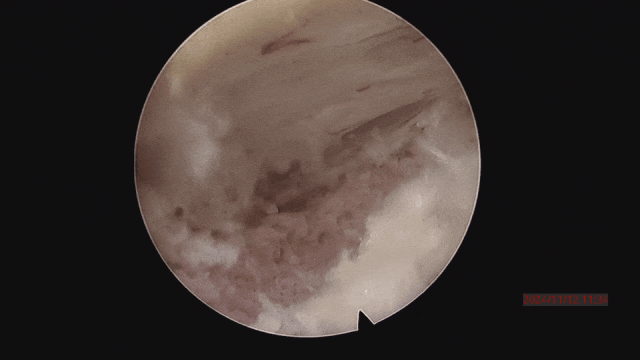

▲取骨块的过程。

▲取骨块后,解除神经压迫。